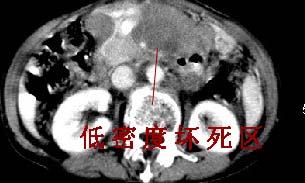

胰腺受压前移,胰管扩张,应为腹膜后占位,病灶密度不均,有低密度坏死区,强化扫描强化不明显腹腔干动脉受侵,考虑腹膜后恶性占位

我的第1诊断还是考虑是淋巴类病变1}。从病灶形态上看不是很规则,但其更向是多个结节的融和,其内有少许坏死,整个病灶的强化不是很明显,临近左恻肠间隔有增厚,2}我认为更重要的一点的是肠系膜有明显增厚呈片状。3}患者的脾脏不大其未见异常病灶。结合以上几点我首先考虑是转移性{但对此诊断我觉得不足之处;转移性的淋巴结肿大融合为什么没有坏死?}。{另外患者无大便习惯改变及血便,其发现右颈包块在今年过年无意发现}。以上是我的浅分析望各位战友继续讨论!谢谢!!

主动脉-胰腺间隙可见巨大分叶状软组织肿块影,包绕腹主动脉、腹腔干及其分支、腔静脉等大血管,增强呈无明显强化,临近脏器明显受压移位,增强示有分界。肝右叶可见局限性低密影,边缘清楚。

考虑腹膜后淋巴瘤。